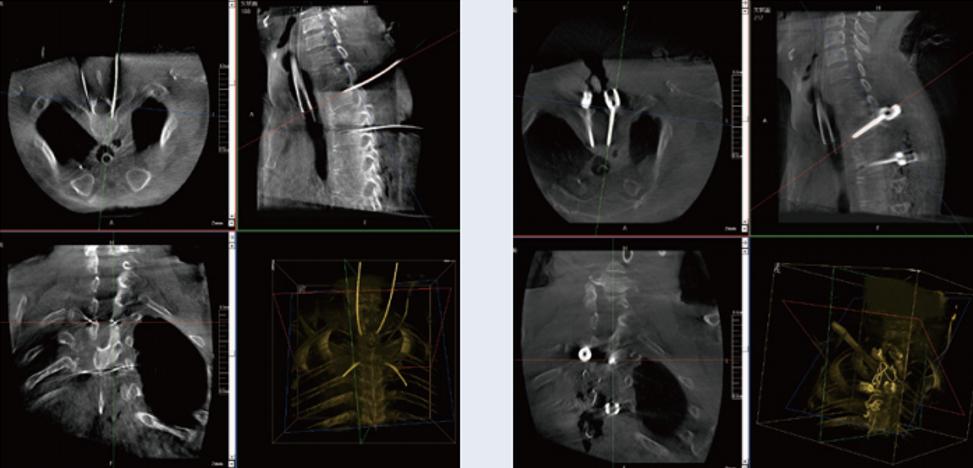

術中使用普愛醫療三維C臂先進行二維拍攝,確認手術部位及骨科導航機器人系統等準備。30cm x 30cm大平板帶來的出色顯示視野可以更好地顯示手術部位全局情況。

在術中行3D掃描成像,為骨科導航機器人系統提供三維空間坐標,確保手術規劃及執行的準確性。

螺釘規劃后的圖像

植入螺釘后的圖像

術中三維C臂與骨科導航機器人配合應用,實現準確定位,確保了手術安全、高效完成。術后二維、三維影像顯示手術效果良好,達到預期目的。

普愛醫療三維C臂提供了高質量的術中實時三維圖像數據,保障了骨科導航機器人手術的準確度和安全性,取得不錯的手術效果。同時,三維C臂特有的斷層成像,能幫助醫生在術中非常直觀地判斷螺釘植入的準確度。